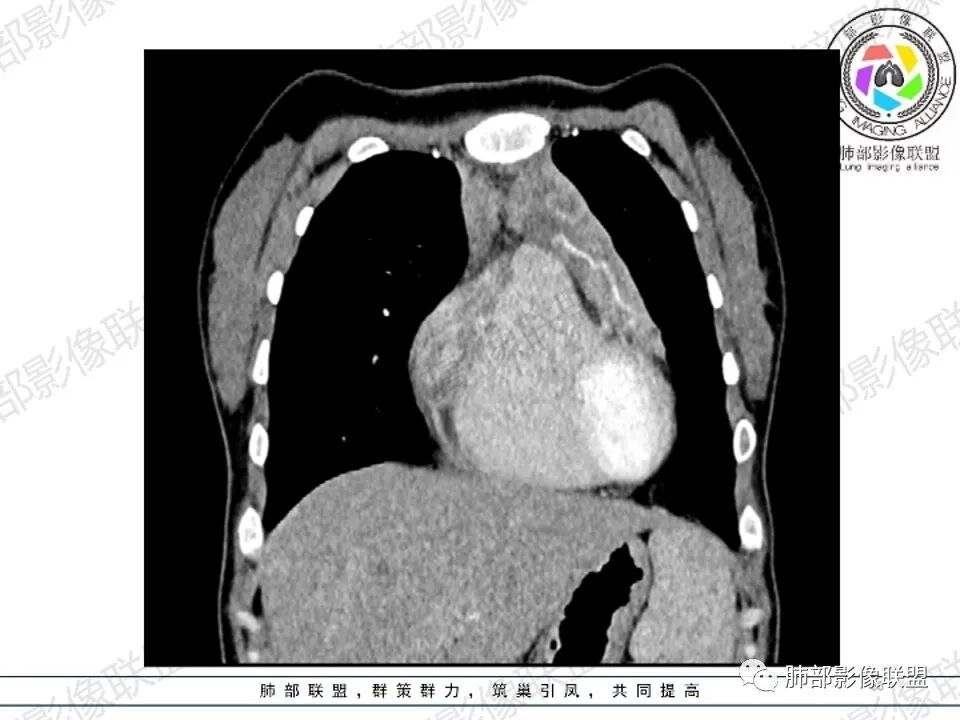

2.影像显示前纵隔不规则块状影,依势贴附心脏大血管旁,密度不均,边界不甚清楚,有结节融合感。

3.病灶轻度不均匀强化,可见血管穿行,散在液性低密度区。

双肺门未见肿大淋巴结。

4.双侧腋窝区见增大淋巴结,边界清楚。